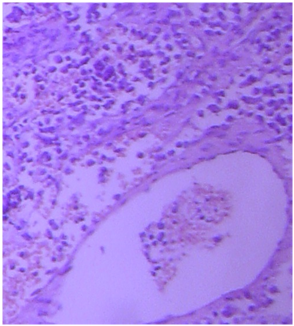

Our case is a 54-year-old male patient who diagnosed as SNNM (Figure 1). His disease was progressed following chemotherapy (CT) and radiotherapy (RT), despite a full response was obtained in the primary tumour with RT. ECOG (Eastern Cooperative Oncology Group) performance scoring was 4, Visual Analog Scoring (VAS) was 100%. His FDG PET CT (Positron emission tomography with fluorine 18 (18F) fluorodeoxyglucose and computed tomography) images showed big tumour in the pancreas and left adrenal gland, the biggest one being 11cm.